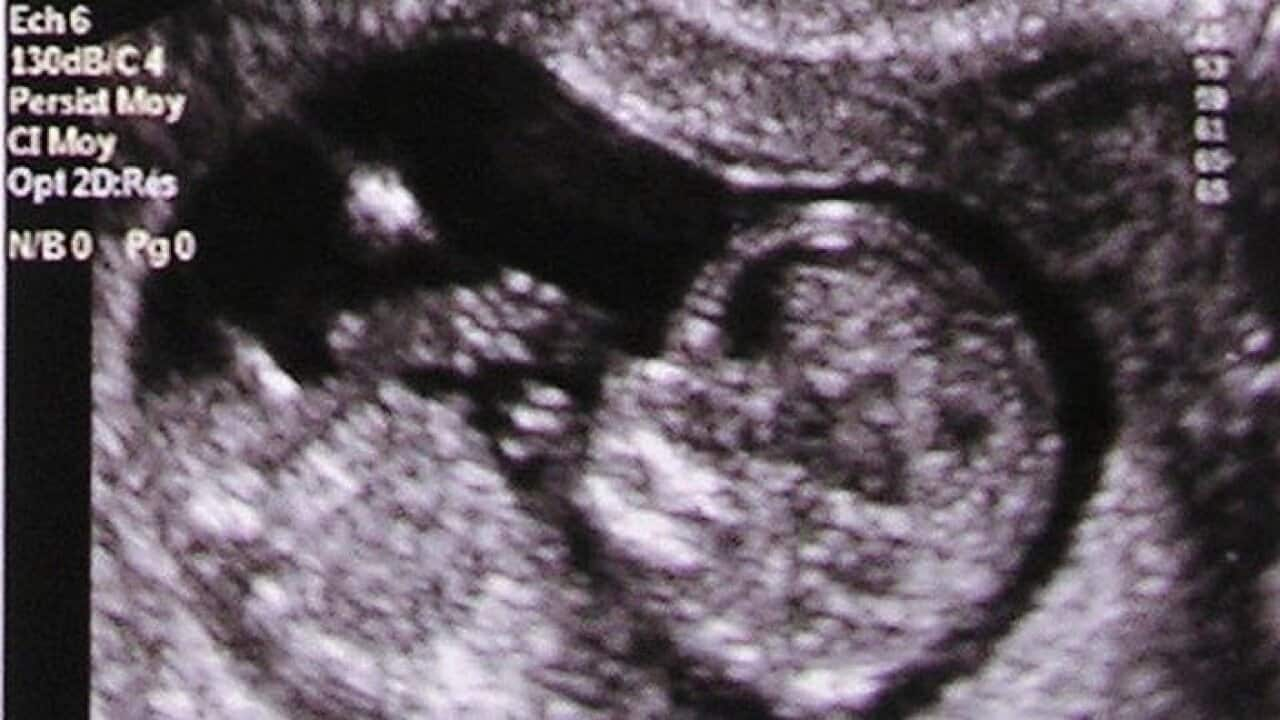

Dibattitu dwar bidla proposta, fl-att tal-protezzjoni tal-embrijuni

Il-korrispondent tal-SBS f’Malta, Leonard Callus jirrapporta dwar id-dibattitu li għaddej f’Malta bħalissa dwar l-emendi proposti mill-gvern fl-att tal-protezzjoni tal-embrijuni.